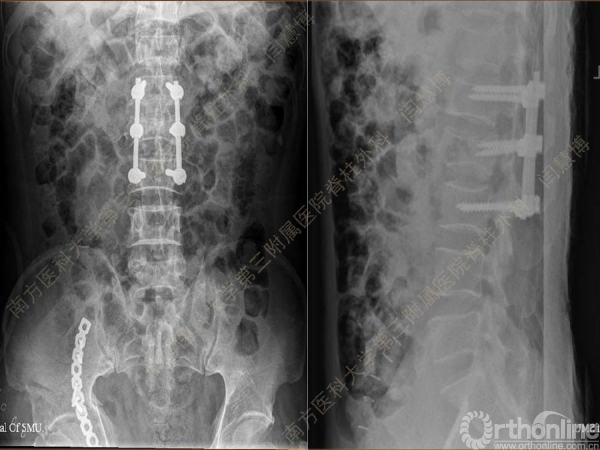

胸腰椎骨折是指由于外力造成胸腰椎骨质连续性的破坏,在如车祸、高处坠落等意外事故中,是最常见的脊柱损伤。老年患者由于本身存在骨质疏松,甚至有可能因为一些如滑倒、跌倒等低暴力因素导致胸腰椎骨折。胸腰椎骨折患者常合并神经功能损伤,且由于致伤因素基本为高能损伤,常合并其他脏器损伤,这为治疗带来了极大的困难和挑战。针对胸腰椎骨折,南方医科大学第三附属医院闫慧博教授介绍了他们运用微创方法治疗的经验。